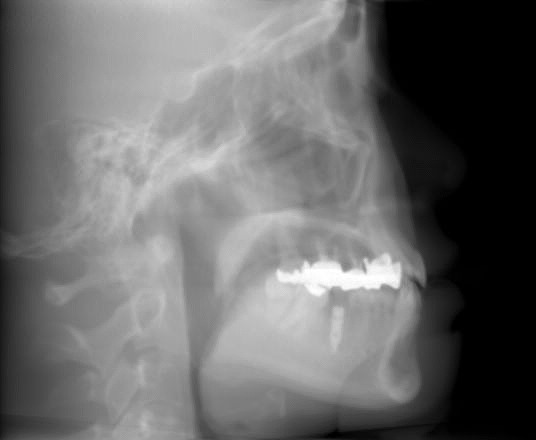

セファロになります